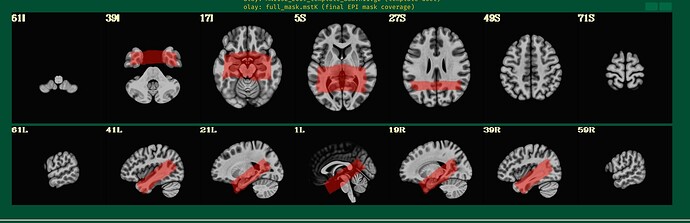

@djunct_overlap_check \

-ulay anat_final.s02+orig \

-olay final_epi_vr_base_min_outlier+orig \

-prefix img_olap

returned